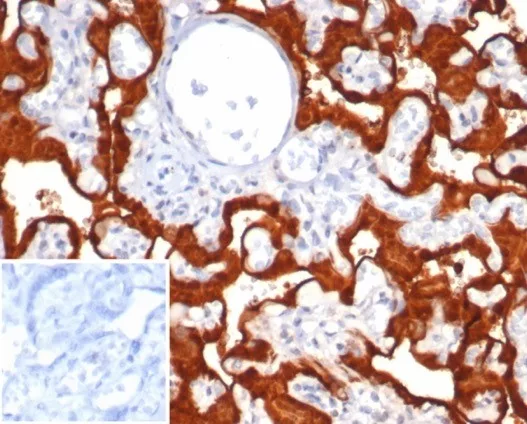

Immunohistochemistry (IHC)

1-2ug/ml

30 min at RT. Staining of formalin-fixed tissues requires heating tissue sections in 10mM Tris with 1mM EDTA, pH 9.0, for 45 min at 95°C followed by cooling at RT for 20 minutes

Human pancreatic adenocarcinoma|placenta or spleen tissue.